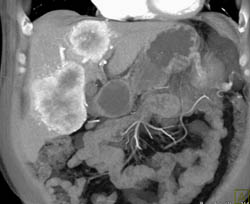

Islet Cell Tumor With Liver Metastases